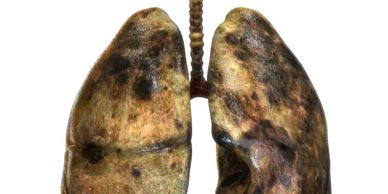

A pair of diseased human lungs with dark spots and damage.

El cancer de pulmon es una de los tumores mas frecuentes en Mexico siendo altamente letal por su diagnóstico tardio, se presenta sin sintomas y actualmente en nuestro pais no tenemos programas de detección oportuna establecidos.  Si eres fumador o tienes antecedentes en la familia de cancer de pulmón cualquier lesion puede ser sospechosa, por lo que requiere un abordaje sistematico y avanzado.